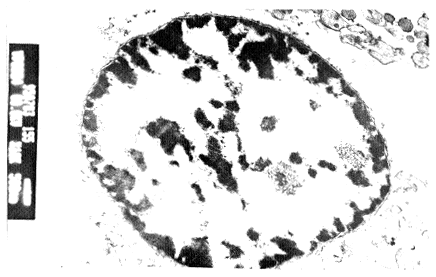

2.4 电镜观察

高剂量rhTNF组LC-6细胞表现为细胞体积缩小,胞膜皱缩,细胞核深染,核内染色质呈块状聚集于核膜下以及凋亡小体形成,见图3。

图3 LC-6细胞形态学观察:细胞体积缩小,核膜皱

缩,细胞核深染,核内染色质呈块状聚集于核膜

下(TEM×10000)

Fig3 LC-6 cell death under Transmission electron micro-

graphs death:Condensation of chromatin and con-

, 百拇医药

tract of the nuclear membrane(TEM×10000)